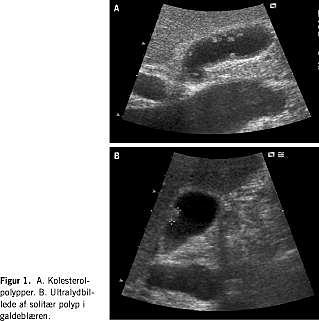

• Galdeblærepolypper ses på ultralydskanninger som små vægstillede hyperekkogene processer, der prominerer ind i lumen uden at kaste stenskygge (Figur 1 ).

• Multiple polypper er ofte kolesterolpolypper, og de er ofte benigne. Solitære polypper er oftere adenomer. De bredbasede polypper er mere malignitetssuspekte end de stilkede.